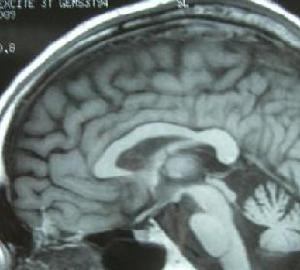

病理改變:顯微鏡下觀察可見脊髓前角細胞減少,伴膠質細胞增生,殘存的前角細胞萎縮大腦皮質的分層結構完整,錐體細胞減少伴膠質細胞增生。脊髓錐體束有脫髓鞘現象而運動皮質神經元細胞完好,表明最初的改變產生於神經軸突的遠端逐漸向上逆行累及大腦中央前回的錐體細胞此種改變又稱為逆行性死亡。一些生前僅有下運動神經元體徵的ALS患者死後屍檢可見顯著的皮質脊髓束脫髓鞘改變表明前角細胞功能受累嚴重掩蓋了上運動神經元損害的體徵。

由於上位運動神經元變性,脊髓側索中的皮質脊髓束的軸索消失和萎縮,髓鞘染色其部位淺染。前角和腦神經運動核的下位運動神經元變性,其結果前根或運動神經的軸索消失、萎縮,變成白色。這些神經元支配的骨骼肌中,產生廣泛的神經源性的肌纖維萎縮。

病變累及錐體束上、下運動神經元,上神經元在大腦皮質,其軸索經過內囊、腦幹及皮質脊髓束與腦運動神經核或脊髓前角運動神經元相聯繫。幾乎所有的病例為散發,發病年齡在40~50歲,男多於女。呈進行性經過,病程2-6年死亡。